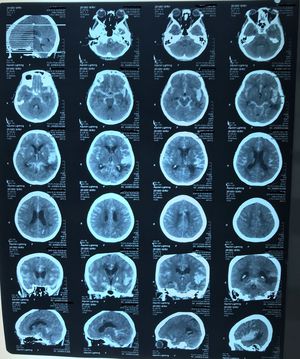

Head CT of patient with moderate head injury

What are abnormal findings can be found in that CT?

SAH, ICH MCA territory , no IVH

sah, ich mca territory. hu? neoplasia? + old infark

SAH with Intra ventricular extension. ICH